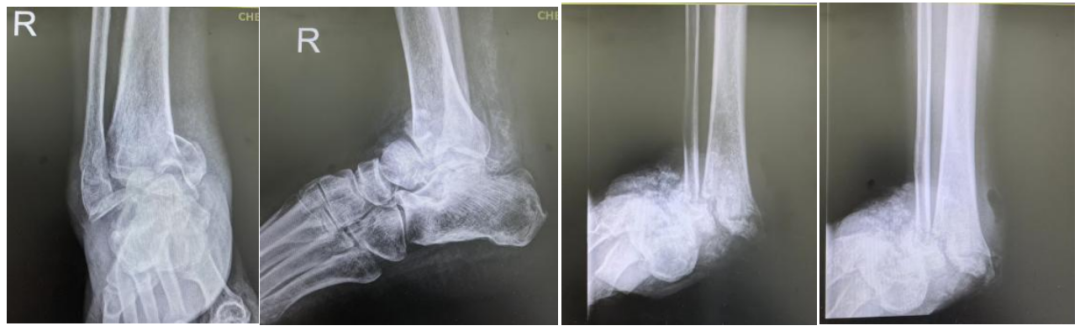

2例典型的踝关节夏科氏关节炎影像学表现